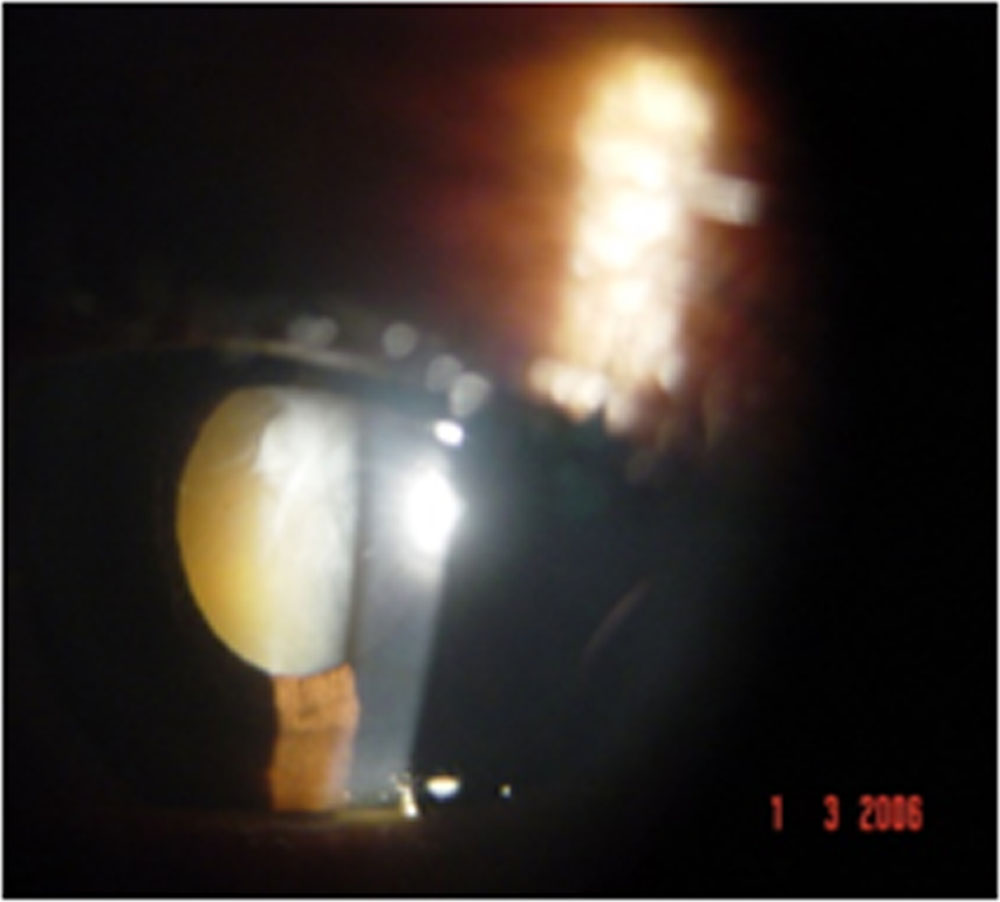

38% showed acute anterior uveitis and 62% showed chronic anterior uveitis. It was granulomatous in 83% with the predominant clinical feature being iris sphincter atrophy and dilated pupil with large mutton keratic precipitatesand anterior chamber cells and flare. 17 % of patients presented with a non- granulomatous iridocyclitis although that is not a usual presentation in uveitis. Cataract was noted in 33% of patients. On morphological evaluation, posterior subcapsular cataract was the most common feature and both senile and complicated cataract were seen. Several of our patients had dilated pupil due to iris sphincter atrophy. Vitritis was present in 3% of patients and was seen as grade 2 cells with vitreous haze. Fundus examination was normal in all patients. 12% of patients had scleritis of the nodular type. Those with scleritis showed resolution with topical steroids with no recurrence and a scraping was not performed on them. Treatment for iridocyclitis was 1% atropine eye drops,1% prednisolone acetate eye drops and oral steroids in the dose of 1mg per kg bodyweight In those with no resolution to this treatment for more than 3 weeks, an anterior chamber paracentesis was performed. RT- PCR performed on the aqueous humour of 12 patients with recalcitrant uveitis showed detection of DNA of M. leprae in 3 of them. A smear in these patients showed the presence of live and dead bacilli. Microscopy showed the typical morphology of fully formed live bacillus and beaded dead bacilli both existing in the same sample. After completion of treatment, the onset of uveitis in the paucibacillary type occurred within 1 year in 9% of patients, 2 years in 33% and within 3 years in 11%. Those with multibacillary leprosy had recurrence of uveitis after 3 years of completion of treatment. No patients had uveitis before that time period.

- Figure 2: Complicated cataract in chronic uveitis

Figure 2: Complicated cataract in chronic uveitis